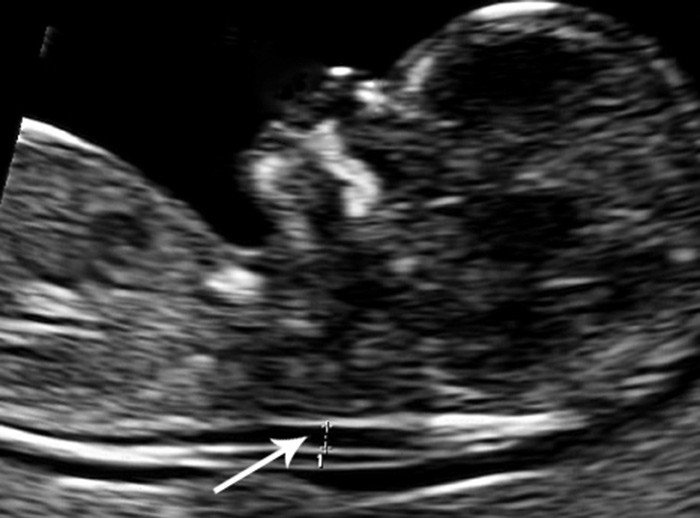

Ultralyd i uke 11 – 13 med måling av nakkeoppklaring (fig 1) og kombinert ultralyd og blodprøve (KUB-test) regnes som fosterdiagnostiske undersøkelser. Nakkeoppklaringen skyldes ødem i nakken hos fosteret, og blodprøvene som tas av mor og inngår i KUB-testen måler konsentrasjonen av humant choriongonadotropin (HCG) og svangerskapsrelatert plasmaprotein A (pregnancy-associated plasma protein A, PAPP-A). KUB-test predikerer sannsynligheten for kromosomavvik eller utviklingsavvik hos fosteret (4) – (6), og metoden ble innført for å unngå komplikasjoner knyttet til invasiv prøvetaking (7). Når ultralydundersøkelser utføres med mistanke om genetisk sykdom, skal det først gis genetisk veiledning. Ultralydundersøkelser i den alminnelige svangerskapsomsorgen, dvs. rutineundersøkelsen i andre trimester og undersøkelser på medisinske indikasjoner, anses ikke som fosterdiagnostikk og omfattes ikke av loven (1, 2).